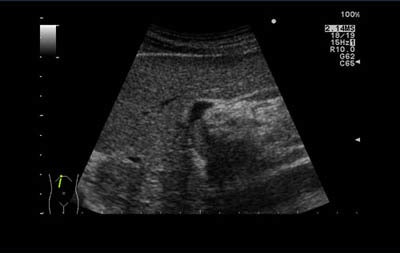

Ultrasound vendor Aloka is working with Dr. Guido Torzilli, an associate professor of surgery at the University of Milan in Italy, to explore the clinical benefits of intraoperative ultrasound in hepatic cancer cases.

Without ultrasound-guided surgery, 35% to 50% of surgical cases require a major hepatectomy. However, using Torzilli's technique means only 4% of surgical cases result in major hepatectomies, according to Aloka.

In one case, Torzilli safely removed 49 lesions from one patient in a single operation. During the next three years, he removed 15 more lesions and left the patient with a functioning liver.

Torzilli said making the need for major hepatectomies around 10 times less likely is "a massive and positive step forward in the care of hepatic cancer patients."